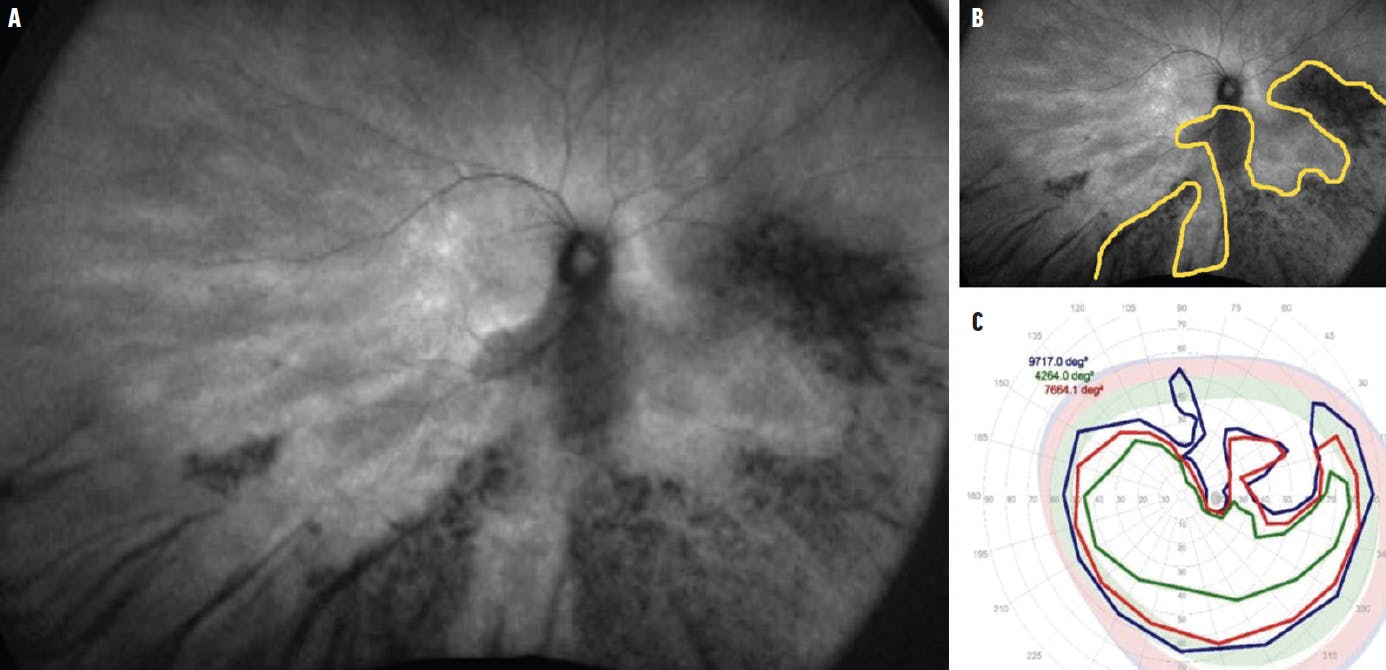

Panretinal photoreceptor dystrophies. Autosomal dominant retinitis pigmentosa (RP) is commonly caused by mutations in the rhodopsin gene, autosomal recessive RP is caused by USH2A gene mutations, and X-linked RP is due to RPGR and RP2 gene mutations. While electroretinography is the standard for diagnosis and monitoring of this disease, FAF can be helpful in phenotype-genotype correlation. On FAF, a hyperautofluorescent parafoveal ring known as a Robson-Holder ring can be seen.12 The ring corresponds to outer segment dysfunction and lipofuscin production. In addition to RP, an autofluorescent ring can also be seen in Leber congenital amaurosis,13 Best disease, cone–rod dystrophies, and X-linked retinoschisis—suggesting a common mechanism.14 Monitoring changes in the size of the ring could be a good outcome marker for rod–cone dystrophies. Outside of this ring, retinal sensitivity is affected, and photoreceptor loss can be seen on OCT; inside the ring, the retina may be normal. Visual fields correlate to the size of the ring.15 Progression of disease may be marked by constriction of the ring, although the ring may expand in cone–rod dystrophy.16 Peripheral hypoautofluorescent changes can be seen in rod–cone dystrophies and are best visualized on ultra-widefield FAF (Figure 3). These changes correlate with visual field constriction and can be used to monitor progression over time.

<p>Figure 3. Ultra-widefield FAF imaging in a patient who is a carrier of an <i>RPGR</i> pathogenic variant (A) shows hypoautofluorescence in the inferonasal retina (B, yellow border), which correlates with Goldmann perimetry that demonstrates superotemporal visual field constriction in all isopters (C).</p>

Figure 3. Ultra-widefield FAF imaging in a patient who is a carrier of an RPGR pathogenic variant (A) shows hypoautofluorescence in the inferonasal retina (B, yellow border), which correlates with Goldmann perimetry that demonstrates superotemporal visual field constriction in all isopters (C).